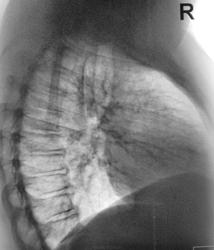

Флюшка, "тень на фоне ребра", сделали контроль..., и вот, в смущении...

округлой формы с распадом, глядя на представленные снимки. См. рисунок. Nikolas

Ничего не понимаю, Валентин Львович, где томограммы? Вы нас так балуете ими, что при таком (!) кругляше их нет? А вообще-то где он на боковом? И не сделать ли косой прицел? Может быть, чем Бог не шутит, такой остеосклероз? конечно, сильно тянет на образование в легком-ТВС, опухоль.

Да, на боковом, лазил, лазил, не нашел. Сделал пару срезов в прямой проекции, но тень - "йок"...

Больше похоже ,что не ребре эта тень. Опять же лучше на скопии посмотреть.

Платность-не всегда порядочность, хотя снимки на руки дать должны были. И чего лечить будем: ТВС или периферию? И то, и другое с элементами распада. Хотя по локализации больше к ТВС.

Мы, сегодня с коллегой фтизиатром, в конце рабочего дня врубились в скиалогию, решили (для себя), что кругляш "мягкая" туберкулома, так как на второй томограмме в окружаюшей легочной ткани узрели очаговые тени. Решили эту "Высокую мадаму" направить на консультацию в ОПТД, а там её, возможно, покрутят и не только в векторе "Величества".

Больше данных за туберкулому, но не исключается и периферический рак лёгкого.